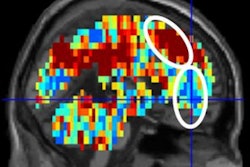

Using functional MRI (fMRI), researchers found unusually high levels of activity in emotional and cognitive brain networks in young adults who had a history of mental illness.

The researchers found many brain regions that were hyperconnected in the subjects with a history of depression. These hyperconnected networks were linked with rumination, in which an individual excessively focuses on a problem without actively trying to come up with a solution. This type of behavior is a risk factor for depression, according to the authors.